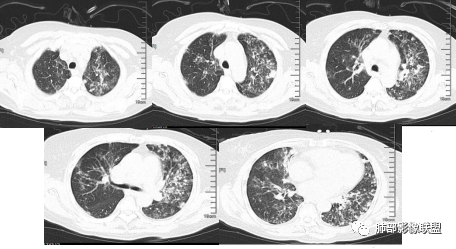

【病例】血源性金黄色葡萄球菌性肺炎1例CT影像

影像与临床:

1.男性少年儿童,外伤后髋部疼痛,畏寒发热、咳嗽、呼吸困难。

休克血压。CRP、PCT明显升高。血气为代谢性酸中毒、呼吸性碱中毒。

2.影像上肺多发混合密度片影,随机分布,胸膜下分布优势,病灶边界大多隐约可辨,偏柔和,动脉血管影穿行,未见钙化、液化空洞、或明确气囊影,未见树芽征。

3.双侧胸腔未见积液。双肺门及纵隔未见增大淋巴结。

4.肝左右叶密度减低,未见结节影、块影或液化区。

综合分析:

1.特别强调:患儿有外伤史,骨关节疼痛,发热,病程短、进展迅速,症状一天之内接踵而至!

2.临床方面:发热,休克血压。CRP、PCT明显升高。血气为代谢性酸中毒、呼吸性碱中毒等等,会高度怀疑脓毒血症!

3.影像方面:双肺多发病灶,随机分布,且有相当部分沿胸膜下,是可以符合血流感染的。

4.责任病原菌:注意是儿童。孩童易外伤,易感染,皮肤粘膜感染、骨关节感染(如急性骨髓炎)是比较常见的,金葡菌感染是多见的,脓毒血症也以金葡为先。只是没有短期复查对比影像资料,不能观察到有无快速出现的气囊影或脓胸等(快速出现的气囊影尤具特征性)。

考虑到宿主因素,以及免疫相关,这个年龄的儿童,无论是G-杆菌还是真菌感染,并不常见。从病程发展看,也没有那么迅捷。

5.补充内容:该患儿并未溺水或呛水。

血源性金黄色葡萄球菌性肺炎具有一些临床和影像学特征:

1.起病急,临床症状重;

2.表现多样,多种影像表现可同时出现,如斑片状影、小点状影、结节影、肺气囊等可在CT片上同时见到;

3.病灶比较广泛,多个肺野出现同时受累;

4.容易在短期内出现散在的肺气囊或多发的脓肿病灶;

5.病灶易变,短期内复查CT可见病灶的形态、部位、大小发生变化。

一、影像特点

1.外围分布,胸膜下为主,两肺弥漫结节或胸膜下楔形影,边界清,周围伴有GGO

2.反晕征:往往紧贴胸膜,并且胸膜侧无环,周围GGO

3.空洞:分为两类。

第一类,偏心空洞,一侧壁厚,周围实变明显。

第二类,薄壁空洞(偏中后期):壁薄且均匀,内外壁光滑,张力高,内有气液平面、间隔影,各空洞相对独立互不相通

4.囊:张力高,壁薄,内外壁光滑,可有间隔

5.边缘收缩明显,结节密实,边缘收缩、凹陷,周围长索条影,提示吸收好转

6.胸腔积液、脓胸

7.增强可见肺动脉栓子(少见)